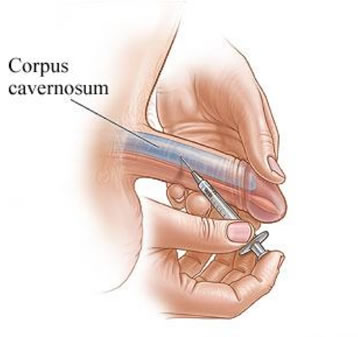

Injections: pain for performance

Some men turn to injections.

And yes, they force the body to respond.

But at what cost?

Sticking a needle in your penis before intimacy.

Pain. Bruising.

And the constant fear of long-term damage.

One older patient admitted:

“It works every time. But who wants to live like that? It kills the moment.”